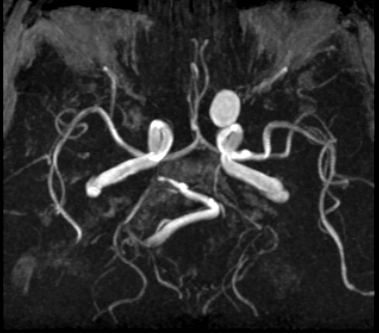

MR angiography (MRA)

Angiographic techniques:

Time of Flight (TOF) is the time it takes for flowing blood to pass through a slice. With the use of very short repetition time, blood vessels will show very high signal intensity (it needs a fast acquisition like Gradient Echo sequence - GRE).

Phase contrast technique (PC) relies on the fact that the flowing spins (the moving protons) lose their phase (desynchronize) faster than stationary tissues. Its advantage is that it can measure flow velocity as well, and it is independent from the direction of the flow.